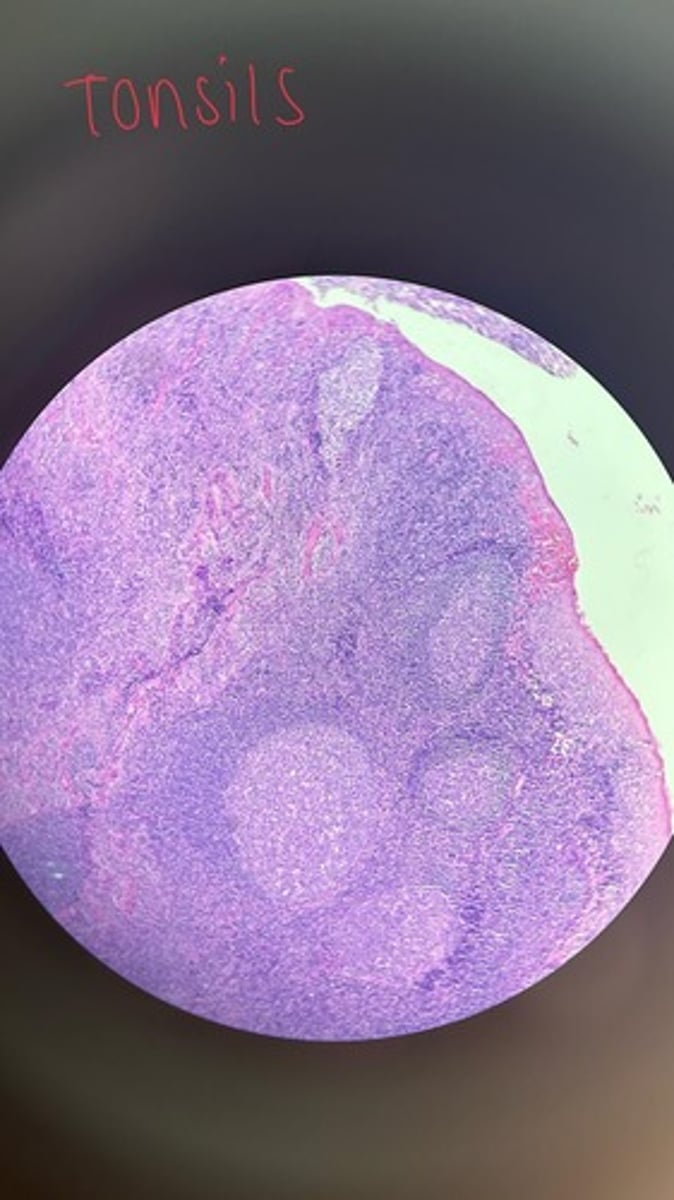

Tonsils HE

Tonsils HE

Tonsils HE